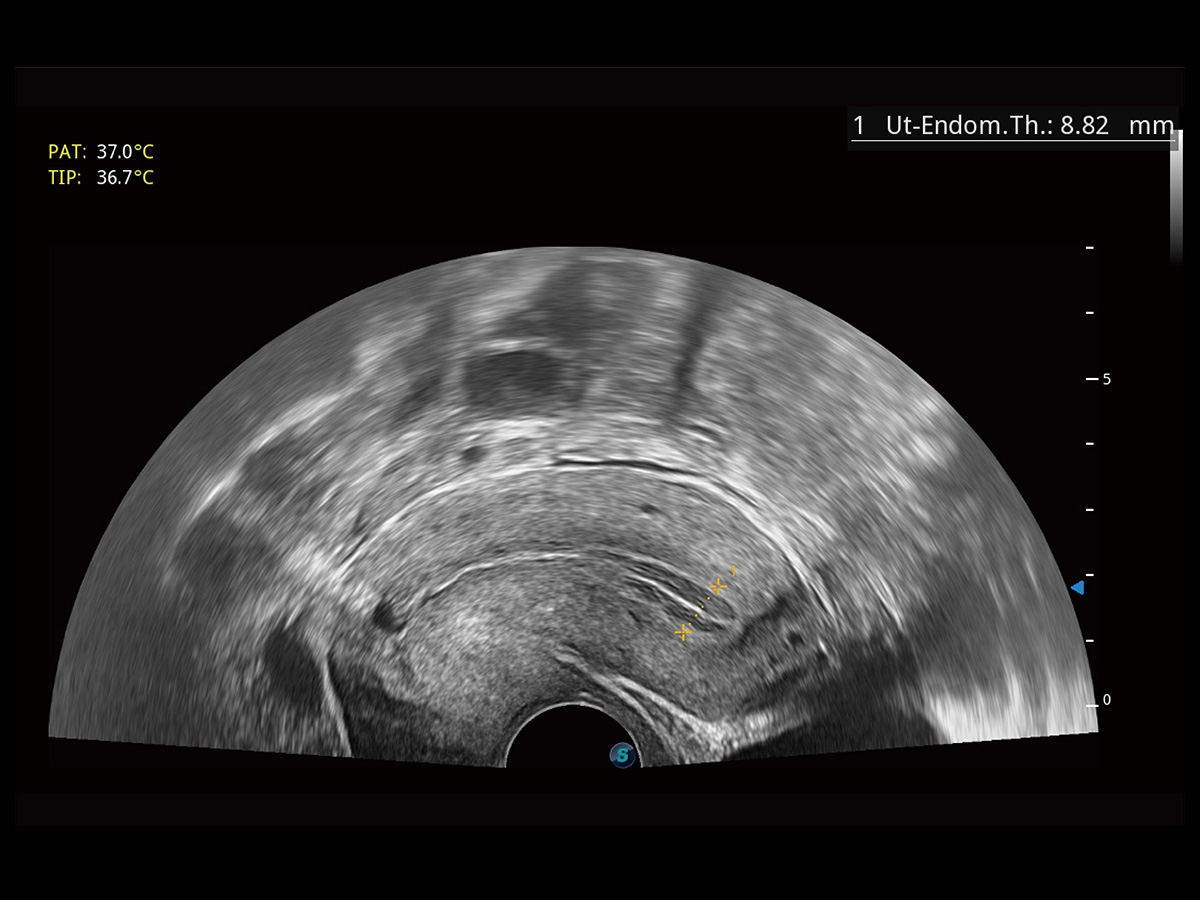

“生育问题”即关系民族复兴,也关系亿万家庭的幸福。随着婚育年龄推迟、社会压力增加等因素,越来越多人群也面临着“生不出、生不好”的问题。辅助生殖作为治疗不孕不育最有效的方法之一,也逐渐成为育儿新希望。而超声检查能为生殖需求人群的初诊评估提供宝贵的信息。 P20 Elite是开立医疗匠心打造的一款生殖应用型彩超。她继承开立医疗高端极光平台,突破性地将多款新型芯片及硬件模块进行整合,均衡了高端系统性能与小巧灵动机身。P20 Elite卓越的图像质量搭载专科探头,旨在为您提供全面的辅助生殖解决方案。

P20 Elite配备了丰富的生殖探头群和临床应用功能,在卵泡监测、穿刺取卵、胚胎移植、妊娠确认等领域,为生殖需求人群提供了新的临床机会,重新定义高端超声如何应用于生殖健康检查。

通过线上云会诊平台,实现县级医院与上级医院患者卵泡数据互联互通。避免重复性卵泡测量,提高诊断效率。